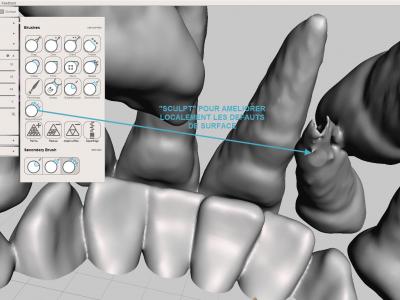

- Etape de finitions : reboucher des manques, adoucir des pics ou des crêtes avec les différents outils "Sculpt"